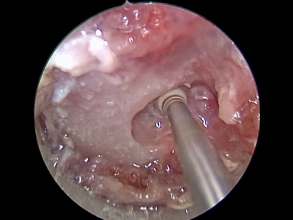

とても小さな2mmのドリル(ラウンドバー)で削っていきます。

とても繊細な手技で神経を使います。せぼねにおよそ6mmほどの穴をあけて椎間板物質をかき出していきます。

右の写真のように使うドリルや鉗子は数mmというとても小さな鉗子を使っていきます。